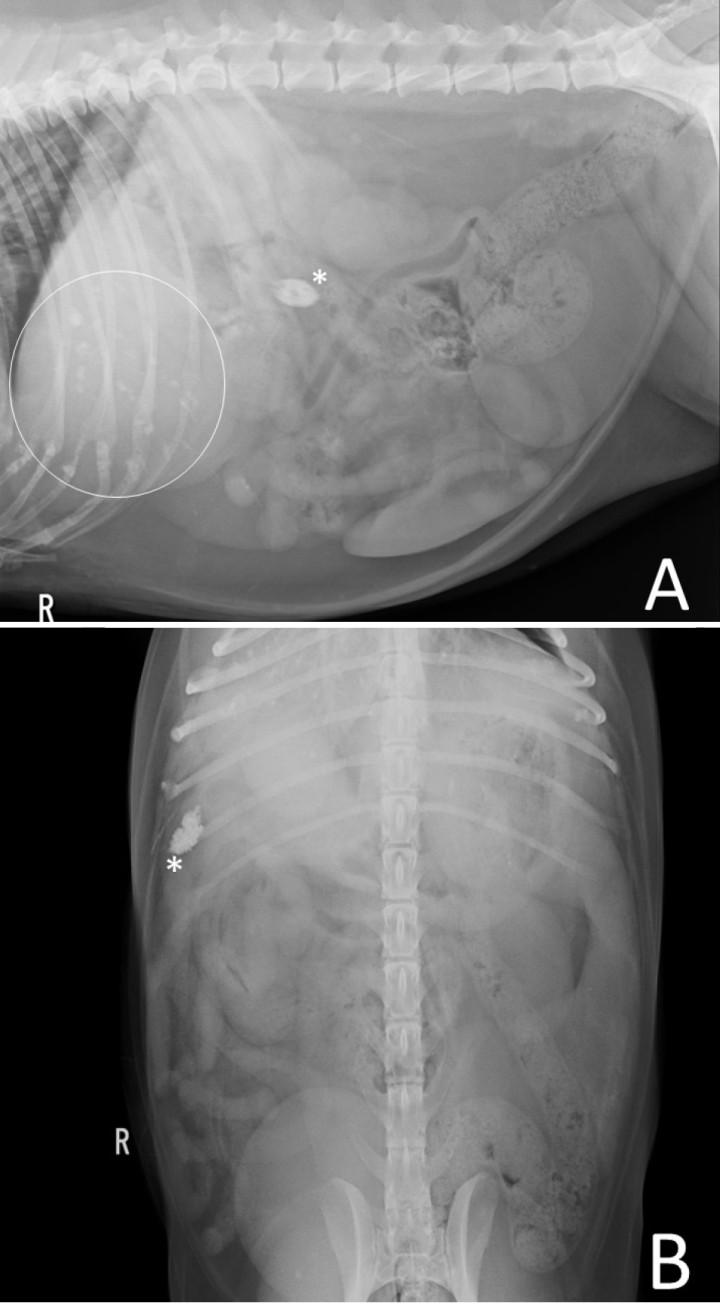

Se realizaron radiografías de la cavidad abdominal, con proyecciones lateral derecha y ventrodorsal (Fig. 1). En la proyección lateral se identificaron múltiples estructuras de opacidad mineral en la región de proyección de la silueta hepática (Fig. 1A) detectándose, además, otra estructura de la misma opacidad con morfología ovalada, bordes irregulares y espiculados situada en el abdomen craneal derecho (Fig. 1B).

<p>Estudio radiográfico de abdomen con proyección lateral derecha (<strong>A</strong>) donde se identifican múltiples estructuras de opacidad mineral (círculo blanco) en la región de la silueta hepática y una estructura de la misma opacidad con morfología ovalada y bordes irregulares y especulados situada en el abdomen craneal derecho (*), como se observa también en la proyección ventrodorsal (<strong>B</strong>).</p>

Estudio radiográfico de abdomen con proyección lateral derecha (A) donde se identifican múltiples estructuras de opacidad mineral (círculo blanco) en la región de la silueta hepática y una estructura de la misma opacidad con morfología ovalada y bordes irregulares y especulados situada en el abdomen craneal derecho (*), como se observa también en la proyección ventrodorsal (B).